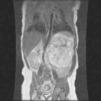

En la RMN se observó un crecimiento de la masa tumoral que desplazaba la aorta, el tronco celíaco, la vena cava y el riñón izquierdo (fig. 1). Se realizó extirpación de una masa macroscópicamente multilobulada, de consistencia firme, con 750 g de peso y 20cm de diámetro (fig. 2). El análisis anatomopatológico confirmó un teratoma inmaduro grado ii (clasificación Norris). La evolución posterior fue favorable junto con una disminución de AFP (63,9ng/ml).

Masa retroperitoneal (10×9,5×8mm) con abundante calcio en su interior y áreas de necrosis. Colección hipoecoica perirrenal. La masa cruza la línea media y desplaza la aorta, el tronco celíaco y la vena cava. Riñón izquierdo volteado con el eje máximo horizontalizado y desplazado hacia la región posterior e inferior.